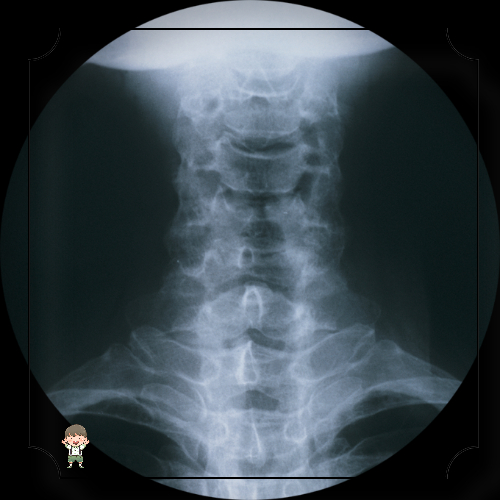

척추 장애 환경

추간판 탈출증: 척추뼈 사이의 추간판이 파열되거나 돌출되어 신경에 압력을 가하는 것입니다.

척추 협착증: 척추관이 좁아지는 증상으로, 종종 노화와 관련이 있습니다.

척추 측만증: 척추의 비정상적인 측면 곡률.